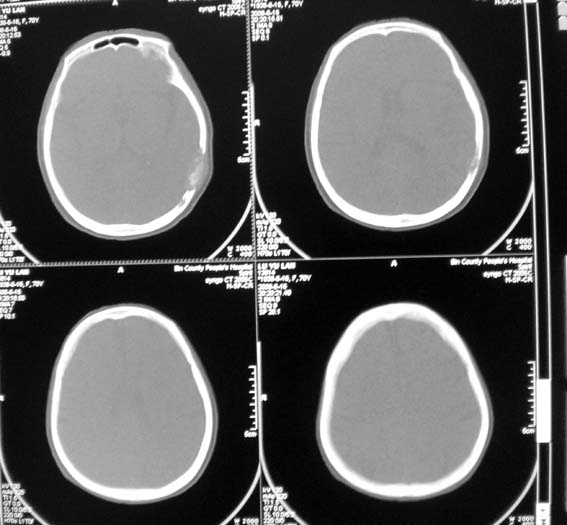

女,70岁,双肺结核,头痛,肿胀包块半年余,逐渐增大。

海绵状血管瘤(硬膜外)可能性大.

溶骨性破坏,未见明确死骨;病灶边缘不整,我考虑为颅骨转移瘤可能性大。建议仔细询问病史,积极寻找原发病灶。肺部如果扫描,最好请一并上传。

ct14067:颅骨破坏结果,转移瘤!

肝脏ct示肝癌,颅骨为转移所致!